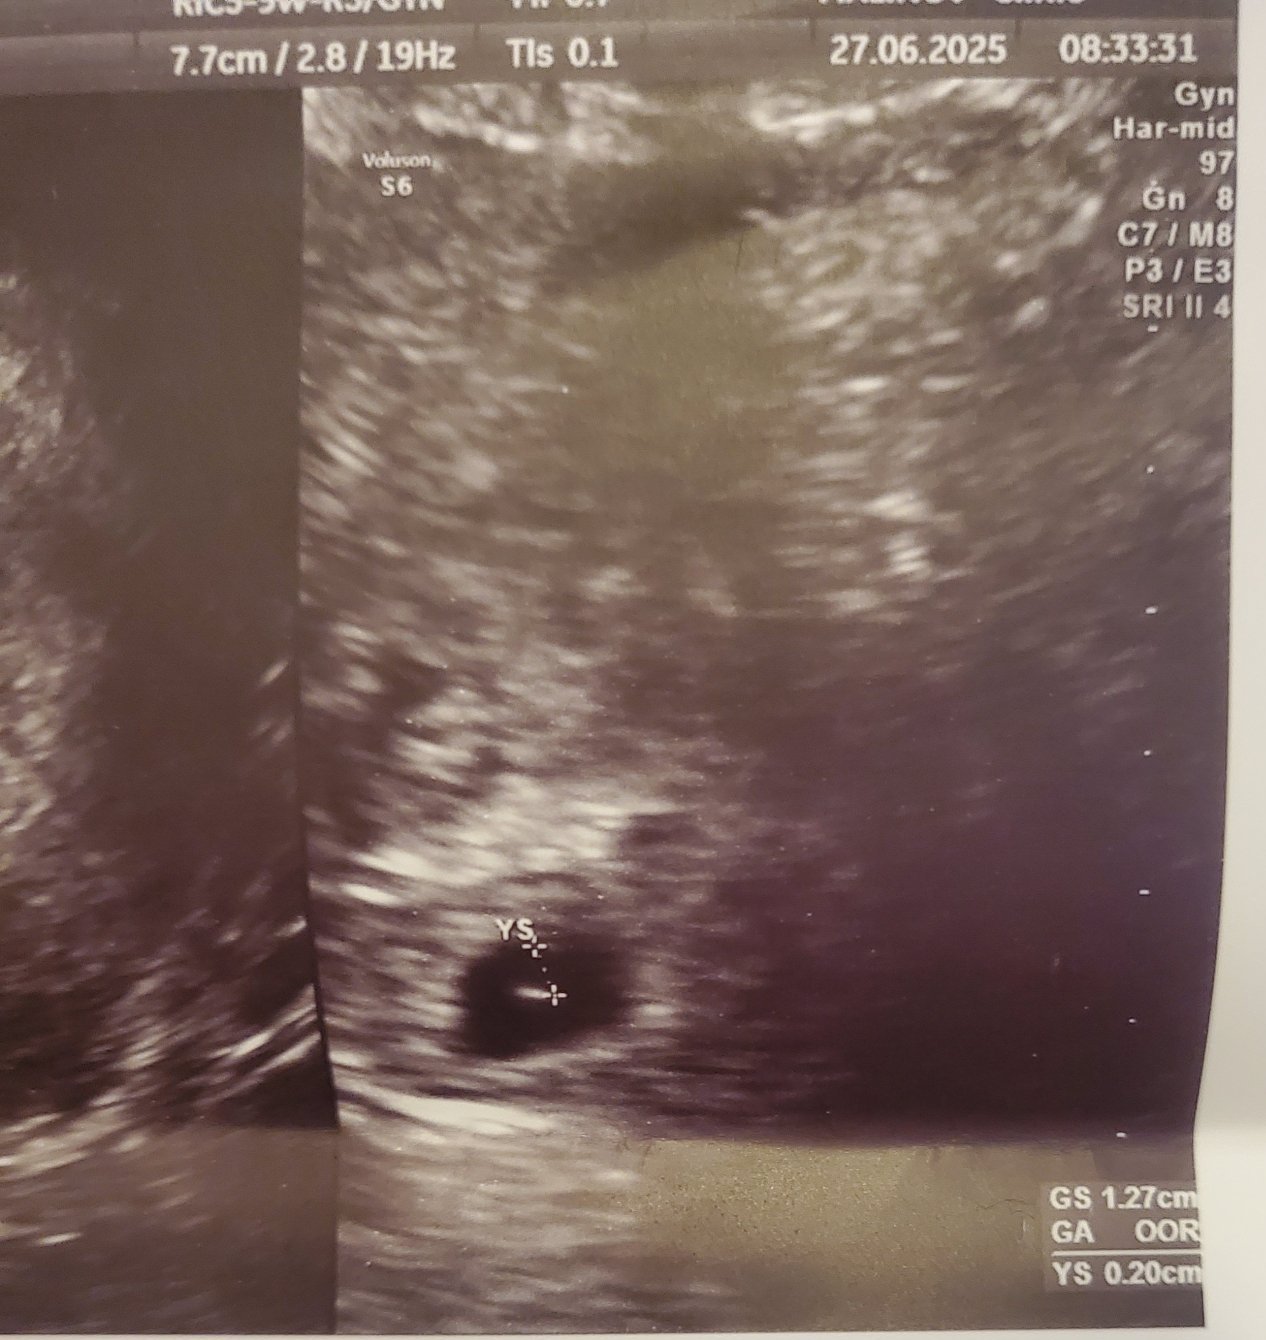

Аз мисля , че вече го няма. Попитах го какво се случва с полипа , той каза "въобще не се притеснявай" имам снимка от преди 10 дни. Утре (7г.с и 3 дни)съм на преглед , за да видим ембриона , защото последния път се видя само жълтъчното мехурче